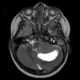

Teratoid tumor

An atypical teratoid rhabdoid tumor (AT/RT) is a rare tumor usually diagnosed in childhood. Although usually a brain tumor, AT/RT can occur anywhere in the central nervous system (CNS), including the spinal cord. [Source: Wikipedia ]